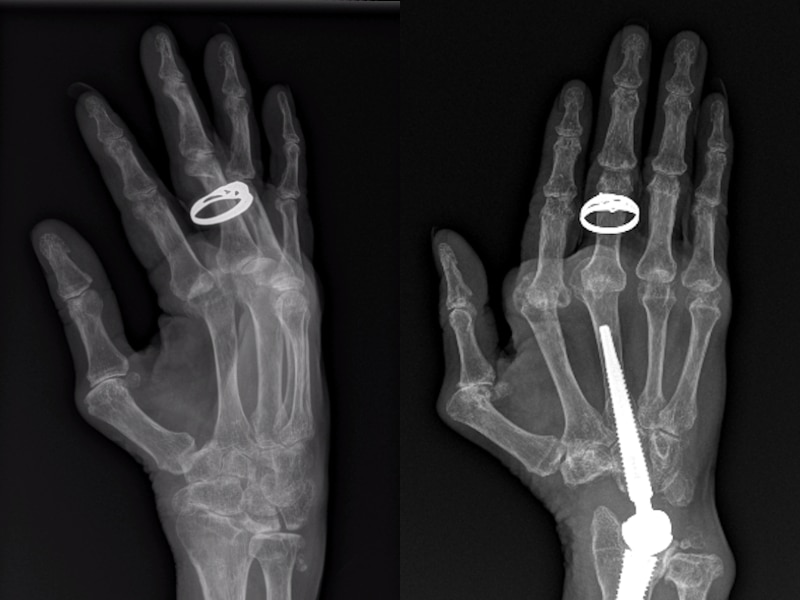

Tracy Howlett uses Auslan to communicate. But it all became "debilitating and painful" after the 59-year-old, who is deaf, was diagnosed with rheumatoid arthritis. Standard surgery for rheumatoid arthritis would create further limitations on Ms Howlett's ability to communicate. So, Queensland hand surgeons performed "unconventional" wrist replacement surgery so she can regain her "voice".

Tracey Howlett, who uses Auslan, got "unconventional" wrist surgery after arthritis made it painful to communicate. Her case promoted further research into how to care for people who are deaf and have develop arthritis. The new study found Auslan communicators required 122 degrees of flexion/extension motion in their wrist and 111 degrees of motion in their elbow to communicate effectively.